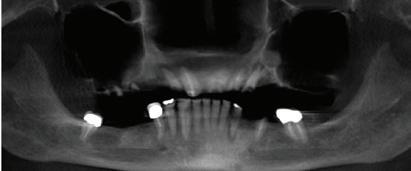

By Farzin Ghanavati , DDS Burke Dental

Missing teeth are more than a cosmetic concern—they can significantly affect your oral health, comfort, and confidence. Fortunately, modern dentistry offers a long-lasting and natural-looking solution: dental implants.

What Are Dental Implants?

A dental implant is a small titanium post surgically placed into the jawbone to serve as an artificial tooth root. Once the bone fuses with the implant in a process called osseointegration, a crown, bridge, or denture can be securely attached. This creates a stable replacement that looks, feels, and functions much like a natural tooth.

When a tooth is lost, the surrounding bone begins to deteriorate because it no longer receives the stimulation that chewing provides. Over time, this can cause changes in facial structure and lead to shifting of nearby teeth. Missing teeth can also affect speech, chewing ef-

ficiency, and self-esteem. Replacing them with implants helps maintain jawbone integrity, keeps adjacent teeth in place, and restores normal oral function.

• Natural appearance and feel –Implants closely mimic the look and strength of natural teeth.

• Durability – With proper care, implants can last decades, often a lifetime.

• Bone preservation – Unlike traditional bridges or dentures, implants stimulate the jawbone and prevent bone loss.

• Improved comfort and function – Implants eliminate the slipping or irritation that can occur with removable dentures.

• No impact on neighboring teeth – Unlike bridges, implants do not require grinding down adjacent healthy teeth.

Who Is a Candidate?

Most healthy adults are candidates for implants. Ideal candidates have sufficient bone density and healthy gums to support the implant. Patients with conditions such as uncontrolled diabetes, smoking habits, or significant bone loss may need additional evaluation or treatment before implant placement.

Implant treatment typically involves several stages: consultation and planning, surgical placement of the implant, a healing period for bone integration, and finally, placement of the crown or restoration. The process may take several months, but the outcome is a strong, stable, and permanent tooth replacement.

Dental implants are one of the most advanced and effective solutions for missing teeth. They not only restore your smile but also protect your oral health for the future. If you are considering replacing a missing tooth, ask your dentist whether implants are right for you.